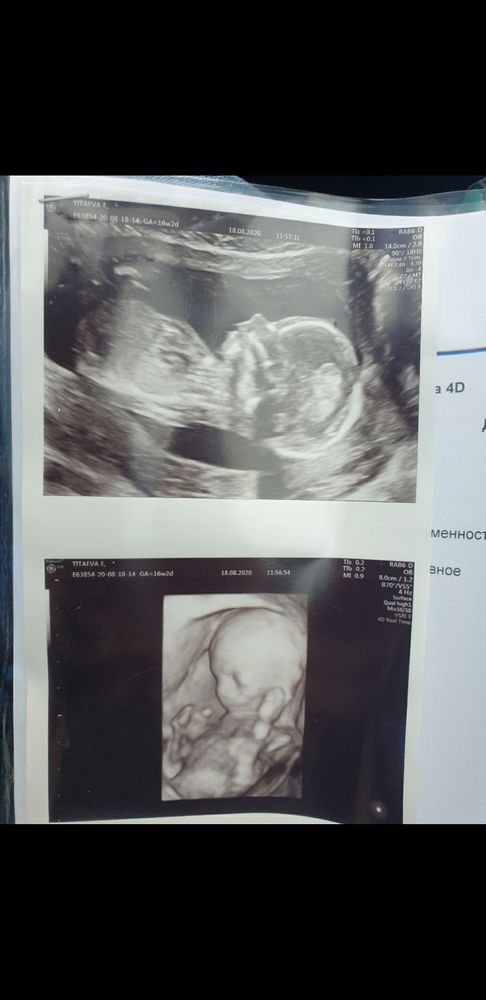

3д узи

Многоплодная беременностьДевочки, стоит ли делать 3д узи на 17 неделе? Многоплодная беременность, может делал кто то, видно там что то или это просто транжирство? Хотела бы примеры глянуть, а то и так трудно материально, стоил ли или нет

Одно фото на 17 неделе, а второе на втором скрининге